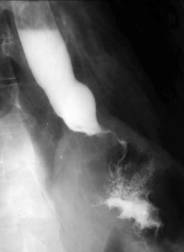

Ingestia accidentala sau voluntara de

substante caustice produce o inflamatie eroziva a peretelui

esofagian. Īn faza acuta, nu se recomanda explorarea imagistica.

Dupa aproximativ 6 luni, evolutia leziunii este completa,

procesele de fibroza si scleroza determinānd stenoza. Dupa

acest interval de timp, prin examinarea cu bariu se pot face aprecieri asupra

existentei, localizarii si gradului procesului de stenoza

Imagistic se observa o īngustare a lumenului esofagian. Zona de stenoza cuprinde un segment lung, localizat de obicei sub strāmtoarea aortica. De cele mai multe ori este asociata cu stenoza gastrica antrala. Alteori se pot forma stenoze multiple, etajate.

Esofagul supraiacent este dilatat, īn pīlnie.